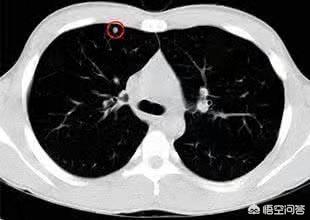

Lungenknoten werden je nach ihrer Dichte in verschiedene Typen eingeteilt: Knoten mit höherer Dichte, die auf dem CT der Brust als weiße Punkte erscheinen, werden als solide Knoten bezeichnet, während Schliffknoten eine geringere Dichte haben und wie Wasserdampf auf dem Glas aussehen. Glasschliffknötchen, insbesondere reine Glasschliffknötchen, sind in der Regel bösartiger.

Erstens werden bei der Einteilung der Lungenknötchen derzeit Lungenknötchen ≥8 mm und ≤3 cm als typische Lungenknötchen bezeichnet, während nur Lungenknötchen <8 mm als kleine Knötchen bezeichnet werden!

Zweitens gibt es einen Zusammenhang zwischen der Größe des Lungenknotens und dem Grad des Risikos, dass er gut- oder bösartig ist! Im Allgemeinen geht man davon aus, dass Lungenknoten <5mm eine 0-1%ige Chance haben, bösartig zu sein; 5-10mm haben eine 6-28%ige Chance, bösartig zu sein; und >20mm haben eine höhere Wahrscheinlichkeit, bösartig zu sein, fast 60% oder mehr, was dem Grad der Bösartigkeit von mattglasartigen Lungenknoten entspricht!

3 Look: Dichte der Lungenknötchen

Die Dichte der Lungenknötchen ist sogar noch wichtiger als die Größe der Knötchen.

CT-Bilder des Brustkorbs werden nach der Dichte klassifiziert, die sie aufweisen:

1. feste Knötchen2.Partieller fester KnotenGemischte gemahlene Glasdichteknollen; 3.nicht fester Knötchen: Vollständig gemahlene Glasknollen.

Die Dichte dieser drei verschiedenen Arten von Lungenknoten in der CT-Bildgebung ist von großem klinischen Wert für die Bestimmung des gutartigen oder bösartigen Charakters von Lungenknoten in Kombination mit anderen Zeichen.